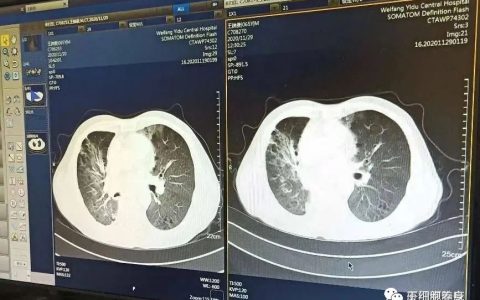

近日,根据媒体报道,67岁的系统性血管炎患者王先生因双足趾皮肤开始发黑,继而出现坏死、溃疡而住院治疗,准备再次进行截肢。入院后,王先生并没有开展截肢手术,而是在血液科专家团队的努力后通过自身干细胞治疗,恢复至能够下床走路。